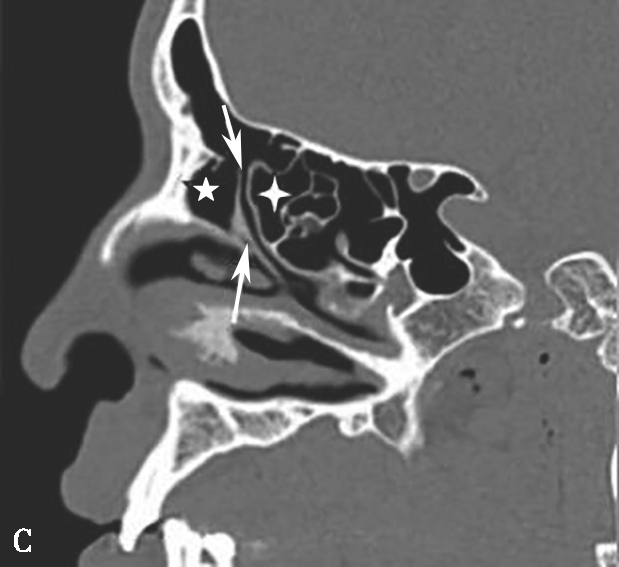

4.筛漏斗(ethmoidal infundibulum)

为筛骨钩突外侧与筛骨迷路间的漏斗形间隙,由前上向后下走行,前部较宽大,为额隐窝,当筛骨钩突前上部起自筛板外缘时,额隐窝为额窦的引流通道;外侧为上颌窦的自然开口;内侧为筛内钩突,后为上颌窦后囟(图1-3-5)。

图1-3-5 筛漏斗解剖

A、B.额隐窝(虚线),鼻丘气房(白箭),额气房(黑箭)